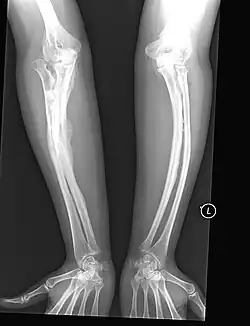

- Encurvamento dos ossos mesmo sem fraturas evidentes;

- Tipo V: Apresentam uma forma moderada da doença com algumas características clínicas e radiológicas distintas, como calcificação da membrana interóssea entre rádio e ulna e/ou tíbia e fíbula, formação de calos hiperplásicos em ossos longos, deslocamento da cabeça do rádio e ausência de dentinogênese imperfeita (DI), mas por mutação do gene IFITM5.

Por ser uma doença que conseguimos ver no fenótipo do portador, há caracteristicas da doença como a esclera azul, dentinogênse imperfeita, déficit auditivo, frouxidão ligamentar, baixa estatura, fragilidade cutânea, cicatrizes hiperplásicas, constipação intestinal, calcificações vasculares e prematuras e doenças na válvula mitral e aórtica, ossos wormianos. No diagnóstico diferencial devem ser consideradas outras doenças como Loyes-Dietz, De Barsy, Marshall-Mitch, e Russel-Silver, em casos clínicos podem ser em casos de alcaptonúria ocronose, síndrome da córnea frágil e malformações múltiplas[4] doença metabólica óssea da prematuridade, osteoporose juvenil idiopática, síndrome de Ehlers‑Danlos, hipofosfatasia, hiperfosfatasia idiopática, síndrome osteoporose pseudoglioma, deficiência de vitamina D e de cálcio[10][11]causas secundárias de osteoporose, incluindo deficiências hormonais, osteoporose induzida por glicocorticoides e leucemia linfoblástica aguda devem ser investigados.[10]Pode também ser confundida com abuso, por conta das fraturas, por isso a importância da avaliação da criança, dos familiares em relação a genética e história clínica para afastar as hipóteses de maus tratos. Fraturas completas ou incompletas da diáfise de ossos longos ou fraturas da coluna vertebral são mais frequentes nos portadores da OI.[4]

As fraturas são tratadas de maneira habitual (redução e imobilização), como em pessoas não portadoras da doença. Ou seja, faz-se a redução do osso e imobilização para regeneração celular. Porém, quando ocorre fratura de crânio pode ocorrer lesão cerebral e morte. Nos portadores de osteogênese imperfeita, ocorre regeneração mais rápida do osso e encurtamento destes, além de angulações dos membros, resultando em crescimento anormal e atrofiado.

Há fontes materiais em arqueologia para fetos intrauterinos com a patologia OI, datando de apenas 38 semanas de gestação. Datado do periodo Bizantino, foi encontrado em Oásis Dakhleh, Egito. Através de uma análise macroscópica e radiológica o esqueleto apresenta uma característica própria de OI com o arqueamento severo dos ossos longos. Este arqueamento é o elemento que resulta na baixa estatura dos indivíduo, é um fator gradual e geralmente apresentado no tipo IV. desta forma, a expectativa de vida de crianças mais gravemente afetadas com OI (tipo II) geralmente não sobrevivem ao período neonatal. Entretando para os tipos I e IV há desenvolvimento pós-nascimento. No tipo III, a expectativa média de vida pode ser encurtada por causa da cifoescoliose grave e formato torácico anormal com doença pulmonar restritiva concomitante e insuficiência cardíaca.[14]